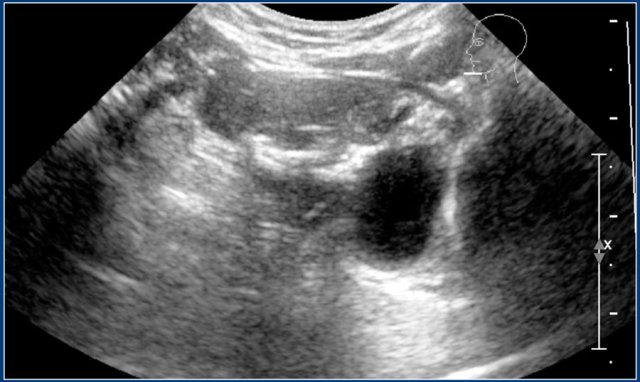

Here an ultrasound of a typical lymphangioma.

MRI was performed because the extension of the lesion was not clear.